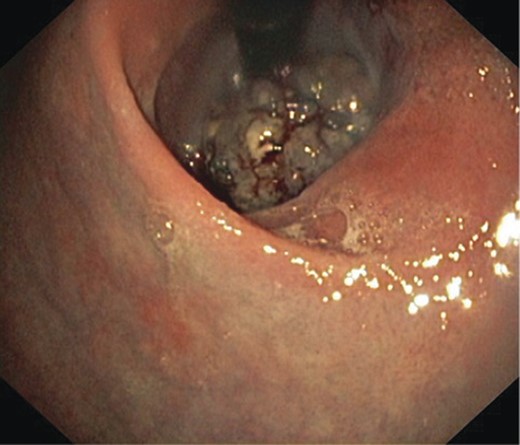

A 75-year-old male presented with a 2-month history of dysphagia, odynophagia and retrosternal post-prandial pain. He had no relevant medical history, and physical, dermatological and ophthalmological examinations proved unremarkable. Barium swallow showed filling defects in the distal oesophagus and subsequent endoscopy found an 8-cm bluish exophytic oesophageal lesion with numerous adjacent satellite lesions and moderate luminal stricturing (Fig. 3). A biopsy result indicated a poorly differentiated malignant melanoma. CT and PET showed an enlarged mediastinal node (not FDG avid) with no evidence of metastases.

An endoscopic view of the oesophageal melanoma with numerous adjacent satellite lesions.